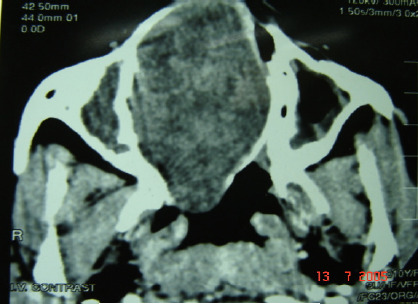

Background: Cellular schwannoma is a benign variant of classic schwannomas. It is an extremely rare condition to be derived from nasal septum.

Case presentation: a cellular schwannoma of the nasal septum is described in a 10-year-old Sudanese girl presented with nasal obstruction. The tumor was treated surgically by a trans-nasal approach. Pathological examination of the resected tumor showed cellular schwannoma. The tumor cells were immunoreactive for S-100 protein. The patient has been doing well for 10 months with no evidence of tumor recurrence.